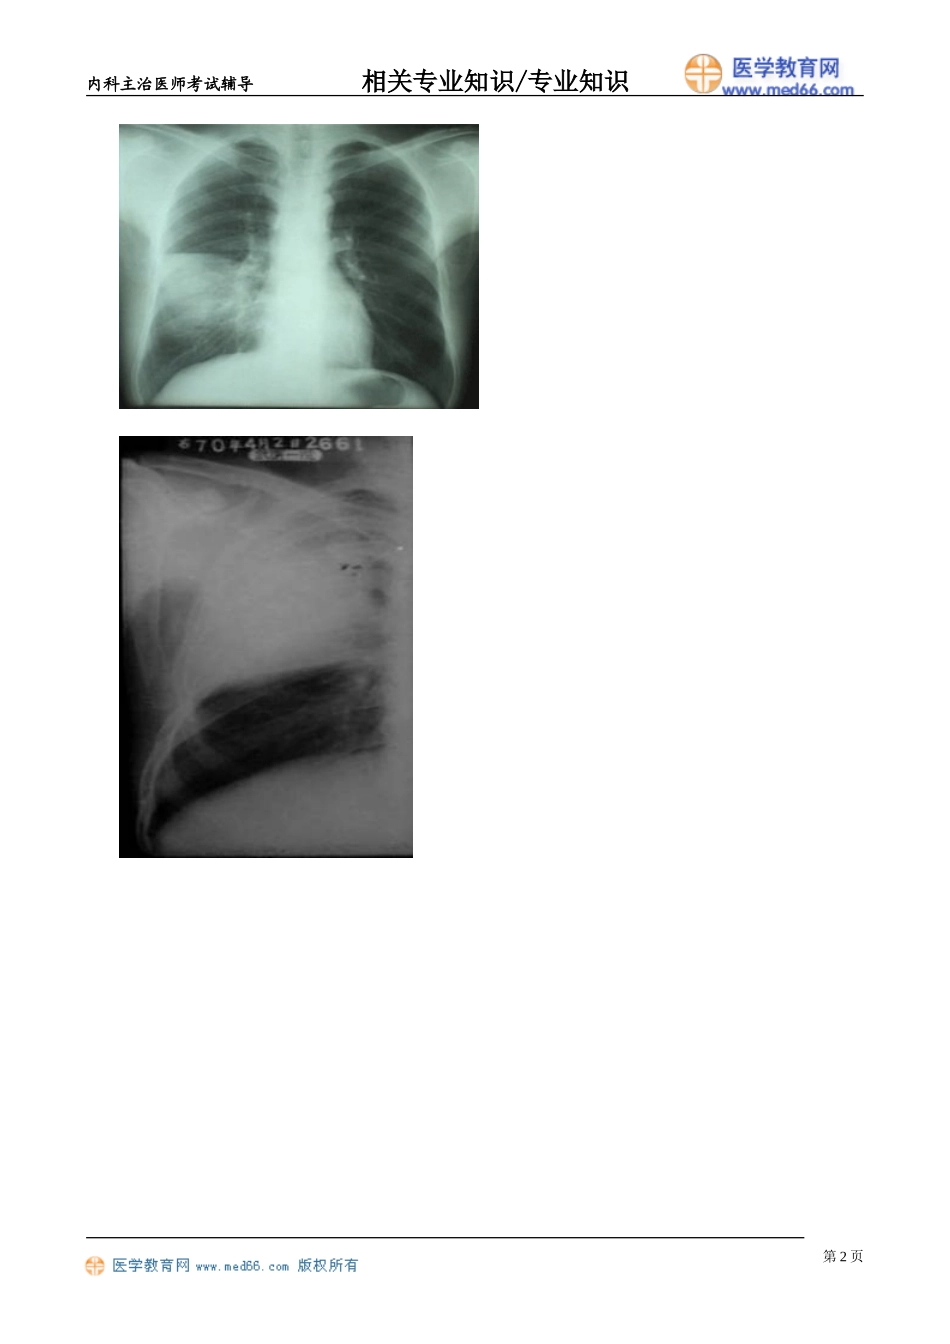

内科主治医师考试辅导相关专业知识/专业知识肺炎分类解剖分类病因分类患病环境分类肺炎的解剖学分类大叶性肺炎:肺泡,单个或多个肺叶或肺段小叶性肺炎:支气管到肺泡间质性肺炎:间质肺叶第1页内科主治医师考试辅导相关专业知识/专业知识第2页内科主治医师考试辅导相关专业知识/专业知识肺内气道社区获得性肺炎:肺炎球菌、流感嗜血杆菌医院获得性肺炎:患者不存在、也不处于潜伏期入院后48小时。无感染高危因素:肺炎球菌有感染高危因素:铜绿假单胞菌、克雷伯杆菌病原体可通过:空气吸入;血流播散;邻近部位;定植菌的误吸第3页内科主治医师考试辅导相关专业知识/专业知识肺炎球菌肺炎第4页内科主治医师考试辅导相关专业知识/专业知识肺炎球菌肺炎诱因症状体征:实变克雷伯杆菌肺炎起病急、寒战高热全身衰竭、痰稠、可呈砖红色、胶冻状肺小叶实变、蜂窝状脓肿、叶间隙下坠氨基糖苷类加半合成广谱青霉素(哌拉西林)名称X线检查痰抗生素临床特点备注肺炎球菌肺炎大片铁锈色青霉素肺实变荚膜葡萄球菌液气囊腔黄色粘稠痰/粉红色乳状脓性痰半合成青霉素或头孢菌素脓并发:气胸或脓胸克雷伯杆菌叶间隙下坠砖红色、胶冻状三代头孢+氨基甙类支原体肺炎斑片状阴影阵发刺激性呛咳大环内酯类儿童发病非典型肺炎有支原体、衣原体、军团菌、立克次体等引起,为细胞内寄生,大环内酯类和四环素类抗生素有效,β-内酰胺类无效主要用于治疗非典型性病原肺炎的抗菌药A.β-内酰胺类B.大环内酯类C.氨基糖苷类D.氯喹第5页内科主治医师考试辅导相关专业知识/专业知识E.磺胺类【答案】:B男,68岁,因脑梗塞住院半月,近一周出现高热咳嗽,咳血痰,查体,T39.2℃,意识模糊,呼吸急促,口唇发绀,双肺散在湿啰音,血常规WBC20.2×109,N0.92.胸片:右肺大片状阴影,其中可见多个气囊腔,该患者最可能的是:A.金黄色葡萄球菌肺炎B.肺炎链球菌肺炎C.肺炎支原体肺炎D.干酪性肺炎E.真菌性肺炎【答案】:A女,38岁,寒战高烧,右侧胸痛3天,查体:T.39.4,意识模糊,右下肺呼吸音减弱,血常规14.3×109,N0.88.胸片示右下肺大片浸润阴影,该患者最可能诊断是:A.克雷伯杆菌肺炎B.肺炎链球菌肺炎C.肺炎支原体肺炎D.干酪性肺炎E.病毒性肺炎【答案】:B女,38岁,干咳、咽痛、发热10天,反复“头孢菌素”治疗无效,查体:T37.7,双肺未闻及干湿啰音。血WBC8.3×109/L,N0.75。胸部X线片示双下肺少许浅淡渗出影。给予阿奇霉素治疗后,症状明显好转。该患者感染的病原体最可能...